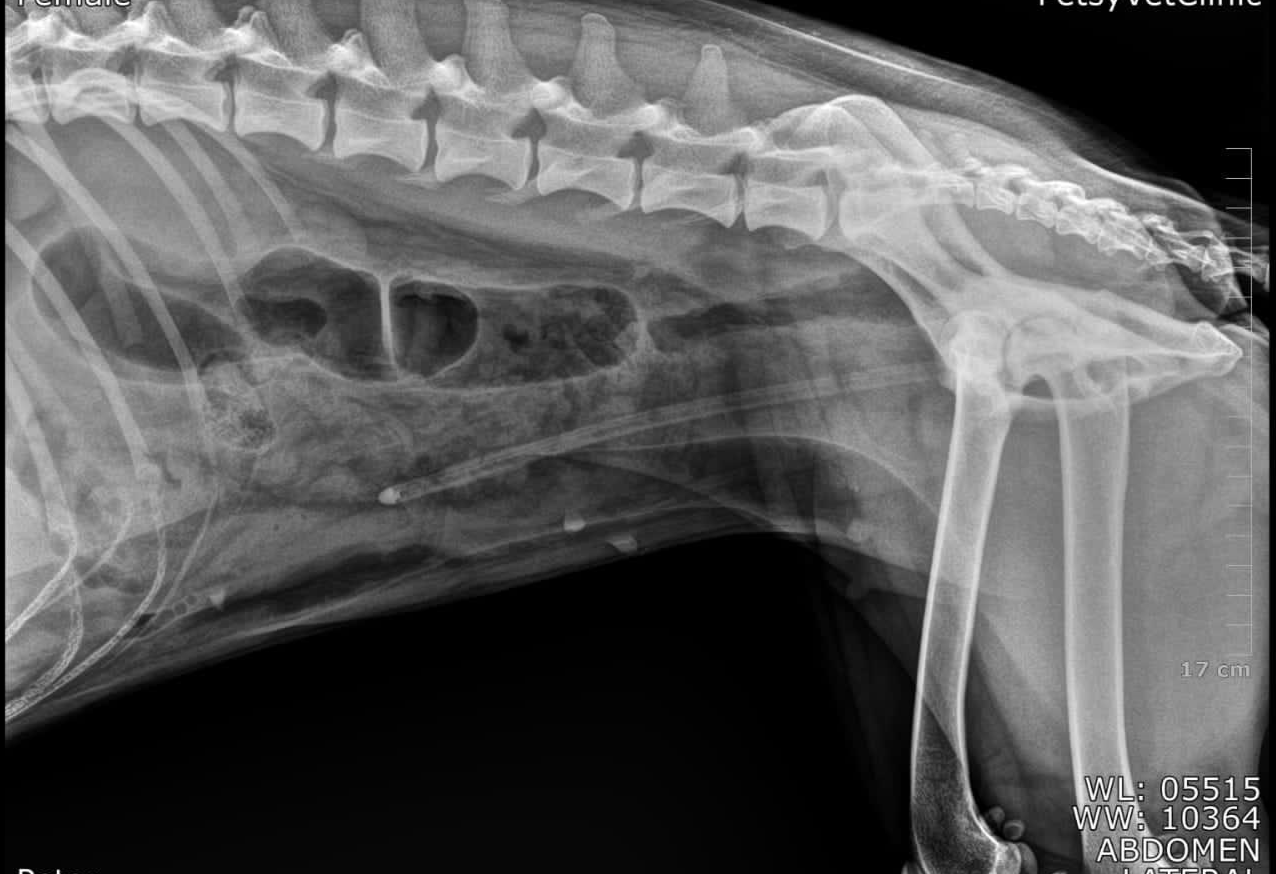

Abdominal radiographs:

show loss of detail (fluid), bladder not visualized, with catheter passing through the bladder to mid abdomen

Xray shows rigid urethral catheter passing through the bladder to mid abdomen